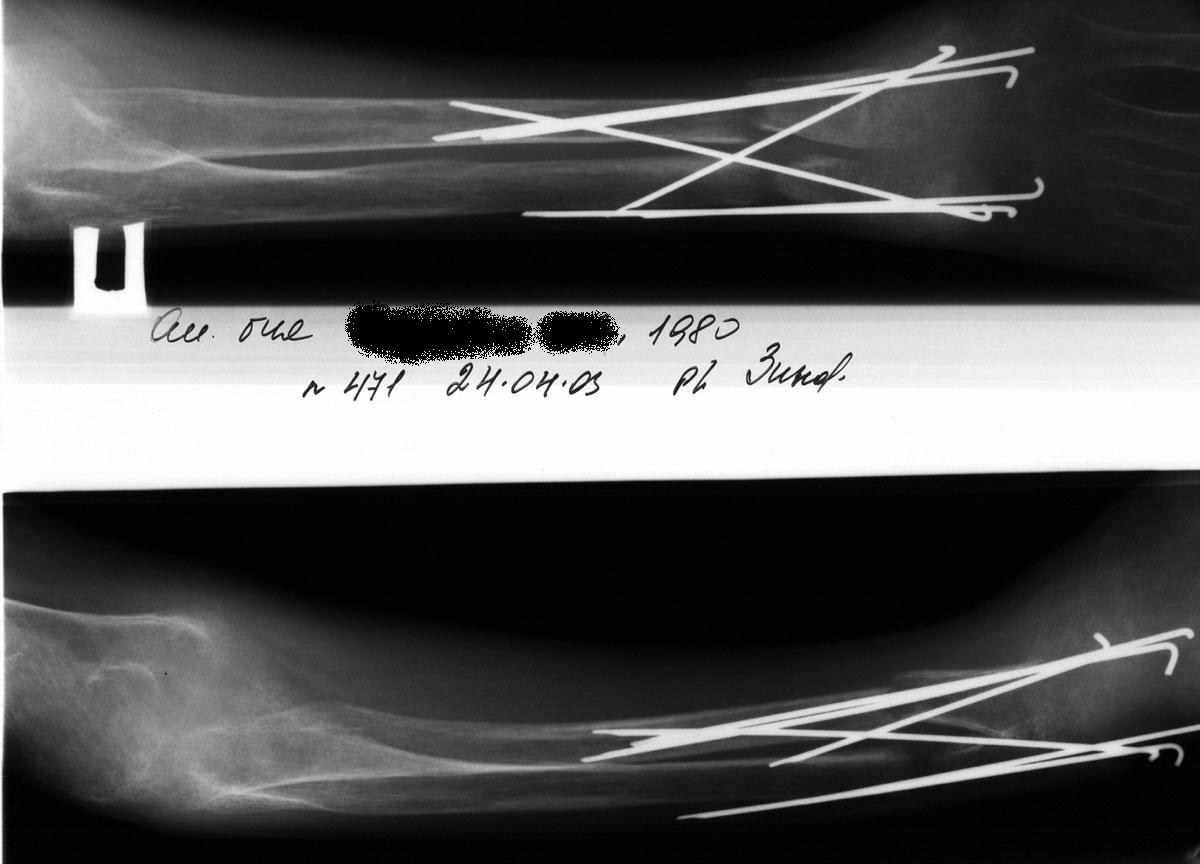

Выписка из амбулаторной карты пациента, 1980 г.р.Находится под наблюдением в поликлинике КНЦ РАН. Состоит на "Д" учёте по заболеваниям:Ювенильный идиопатический генерализованный остеопороз. Деформация грудной клетки за счёт множественных переломов грудины, рёбер. S-образный кифосколиоз грудного отдела позвоночника.Синдром гипофосфатемии неясного генеза. ВСД по кардиальному типу.Инвалид 1-й группы с детства. Последние 4 года не может передвигаться, возникают патологические переломы. Живёт в семье, материально-бытовые условия удовлетворительные.За последние 2 года состояние значительно ухудшилось - усилилась общая слабость, участились патологические переломы, которые не срастаются. Постоянно лежит в постели. Постоянный приём препаратов кальция и диеты с повышенным содержанием кальция, фосфора и белка эффекта не дают. С 11.07.2002 по 30.07.2002 г. лечился в травматологическом отделении АЦГБ с переломом костей правого предплечья со смещением. С 24.08.2002 по 08.09.2002 г. лечился в терапевтическом отделении по поводу острого бронхита с бронхоспастическим компонентом.На сегодняшний день статус. Состояние относительно удовлетворительное. В сознании. Положение вынужденное: сидя в инвалидном кресле, сам встать на ноги и передвигаться не может, туалет только с помощью родственников. Бледный, астеничный. Выраженная деформация грудной клетки, выраженный кифоз и сколиоз грудного отдела позвоночника. Экскурсия грудной клетки ограничена. Участие в акте дыхания вспомогательных межрёберных мышц. Пальпация грудной клетки безболезненна. Деформация всех крупных и мелких суставов за счёт увеличенных эпифизов. Деформация длинных трубчатых костей, мышцы рук и ног атрофичны. Температура - 36,8, ЧД - 29 в минуту. Дыхание жёсткое, проводится во все отделы. Слева от угла лопатки и в аксиллярной области влажные мелкопузырчатые хрипы, в межлопаточной области с обеих сторон свистящие хрипы. Пульс 90 ударов в минуту, ритмичный, симмитричный, слабого наполнения и напряжения. АД 120\80 мм рт. ст. Границы относительной сердечной тупости не расширены. Тоны сердца громкие, ритм правильный. Язык влажный, блестит. Живот при пальпации мягкий, не вздут, симметричный, участвует в акте дыхания, безболезненный. Печень по краю рёберной дуги. Стул регулярный, оформлен, без патологических примесей. Мочеиспускание свободное, безболезненное. Симптом Пастернацкого отрицателен с обеих сторон. Отёков нет.Анализ крови общий 26.08.2002: Hb-146 г\л, Эр.-4,8, ЦП-0,91, Лейк.-6,4, п.-4, с.-45, э.-5, м.-11, СОЭ-4 мм\ч.Анализ мочи общий 26.08.2002: Уд. вес-1025, белок-0,01, сахар-нет, лейк.-0-1 в поле зр., слизь+++, бактерии+.Анализ крови биохимический 26.08.2002: глюкоза-4,9, АЛТ-0,3, АСТ-0,5, биллирубин-11,9, креатинин-44,2, мочевина-3,8, СРБ (+).Анализ крови на микрореакцию - отрицательный.Флюрограмма за 2002: Резко выраженная деформация грудной клетки за счёт множественных переломов рёбер, грудины. Инфильтративных теней в лёгких не определяется. По сравнению с предыдущим исследованием от 01.12.2000 г. - ухудшение: нарастают деформация грудной клетки и позвоночника.ЭКГ за 2002 год: Синусовая тахикардия с ЧСС 88 в минуту. Отклонение ЭОС вправо. Признаки нарушения процессов реполяризации миокарда задней стенки левого желудочка. Повидимому, изменения ЭКГ обусловлены позиционными изменениями, возможно астеничным телосложением.Дополнительные методы исследования.Рентген правого предплечья (17.10.2002): Металлоостеосинтез по поводу перелома обеих костей правого предплечья в н\з: признаки репарации практически не определяются, сохраняется диастаз между отломками.Рентген правого предплечья (24.04.2003): Металлоостеосинтез по поводу перелома обеих костей правого предплечья в н\з: признаки репарации отсутствуют, формируются ложные суставы. Резко выраженный остеопороз.Рентген правого бедра (18.02.2003): Несросшийся перелом правого бедра на границе с\з и н\з со смещением отломков под углом открытым кнутри. Формирующийся ложный сустав. Выраженный остеопороз костей.Рентген правого бедра (24.04.2003): Угловое смещение отломков правого бедра увеличилось. Признаки репарации крайне вялые: по наружному краю отломков формируются замыкательные пластинки - ложный сустав. Выраженный остеопороз.

А чего собственно консервативным? Это к остеопорозу от бездействия приведет еще больше. Уж если взялись лечить диафизарный перелом, то лучше бы его было хорошо сопоставить и фиксировать, идеально закрыто стержнем. Можно и

аппаратом, используя спицы с упорами, проводимые на разных уровнях. А на примере предплечья здесь - и вроде что-то делали, а в то же время и

сопоставления хорошего нет, и фиксация нестабильная, и из-за пучков спиц этих функция мышц нарушена... То бишь все условия для форомирования ложного сустава.